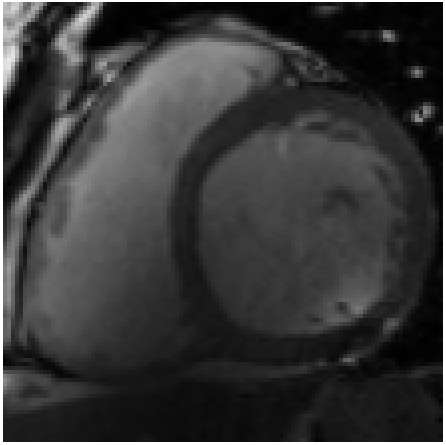

Figure 4: Qualitative evaluation of reconstruction performance of our method on cardiac cine MRI (ACDC dataset). (a) Original cardiac MRI scan; (b) Its reconstruction and (c) Differences between original (minuend) and corresponding reconstructed (subtrahend) slice. Note that to reconstruct a slice xnsubscript𝑥𝑛x_{n} the mixing coefficient α𝛼\alpha in Equation 1 is set to zero. Blue corresponds to negative and red to positive differences. Image intensities are scaled to a [0,1]01[0,1] range. All difference images use the same color scale [1,1]11[-1,1].

Slice Reconstruction: Results for reconstructed and synthesized slices listed in Table I convey that the proposed approach achieved high reconstruction performance especially in terms of SSIM and PSNR. Figure 4 depicts qualitative results of reconstruction performance for the proposed method on cardiac MRI. The results show that the trained autoencoder can reconstruct high-quality images i.e. input slices. Nevertheless, difference image shown in Figure 4(c) depicts that some high spatial frequency details of the input slice are lacking in the reconstructed slice.